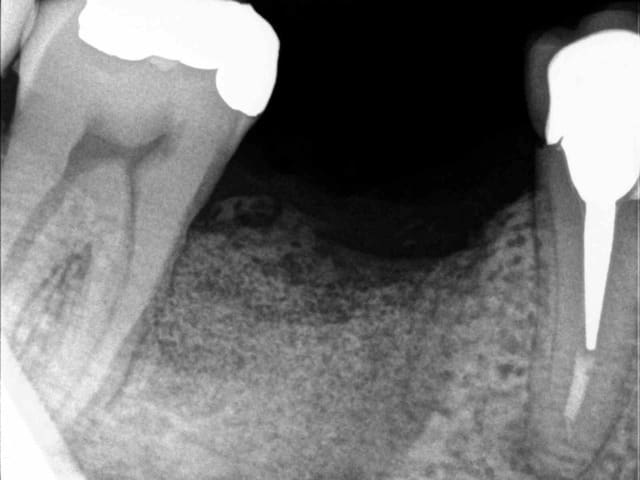

patient qui consulte lundi dernier pour avis implantaire pour 46

je regarde et je vois un petit morceau osseux bien vilain qui dépasse.

l'extraction a eu lieu il y a 4 mois par un confrère qui bosse bien et donc je ne remet pas en cause ses compétences.

l'extraction s'est pourtant bien déroulée et d'après le patient, les suites aussi. là j'en doute un peu plus mais bon...

je lui ai programmé rapidement une intervention pour ce matin afin de cureter.

il a simplement fallu tirer un peu sur le séquestre